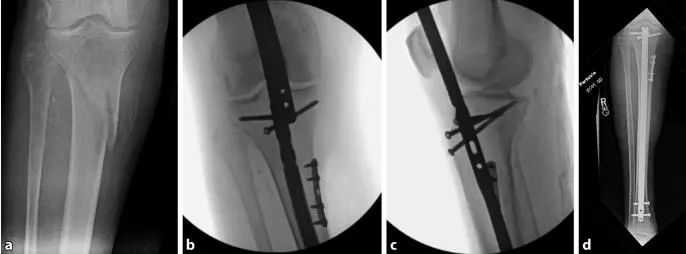

បច្ចេកទេសក្រចក intramedullary សម្រាប់ការបាក់ឆ្អឹង tibial: តាមរយៈ suprapatellar វិធីសាស្រ្ត transarticular ជាមួយជង្គង់ flexed នៅ 20-30° និងបំពង់ការពារជាក់លាក់មួយដើម្បីការពាររចនាសម្ព័ន្ធខាងក្នុង។

មូលហេតុចម្បងនៃការខូចទ្រង់ទ្រាយនៃការបាក់ឆ្អឹង tibial គឺការខូចទ្រង់ទ្រាយដែលបណ្តាលមកពីការទាញសរសៃពួរ quadriceps កំឡុងពេលបត់ជង្គង់ និងការប៉ះទង្គិចមេកានិចរវាងចុងក្រចក និង Cortex tibial ក្រោយអំឡុងពេលដាក់បញ្ចូល។ patella ក៏ការពារការចូលតាមអ័ក្សនៃក្រចកនៅក្នុងយន្តហោះ sagittal (រូបភាព 1a, ខ) ។ ដូច្នេះ វិធីសាស្ត្រទូទៅមួយទៀតនៃការចូលទៅក្នុងចំណុចគឺតាមរយៈស្នាមវះ medial parapatellar ដែលនាំឱ្យមានការបញ្ចូលក្រចកពីកណ្តាលទៅចំហៀងបន្តិច (រូបភាព 1c និង 2)។ នៅពេលដែលក្រចកចូលទៅក្នុងប្រឡាយ intramedullary distal ដល់ការបាក់ឆ្អឹង ផ្នែកជិតៗត្រូវបានផ្អៀងទៅជា exostosis (រូបភាពទី 2)។ ទីបំផុត ភាពតានតឹងនៃការសម្រាកនៃសាច់ដុំអង្គជំនុំជម្រះខាងមុខបានរួមចំណែកបន្តិចបន្តួចដល់ ectropion (រូបភាពទី 3) ។

រូបភាពទី 1 a,b ដោយប្រើវិធីសាស្រ្ត infrapatellar ធម្មតា patella ការពារការចូលតាមអ័ក្សនៃក្រចក ដែលបណ្តាលឱ្យមានការខូចទ្រង់ទ្រាយទូទៅនៃការតម្រឹម apical sagittal anterior និង ectropion coronal alignment.c ការតម្រឹមក្រចក intramedullary ត្រូវបានអនុវត្តដោយប្រើវិធីសាស្រ្ត parapatellar ។